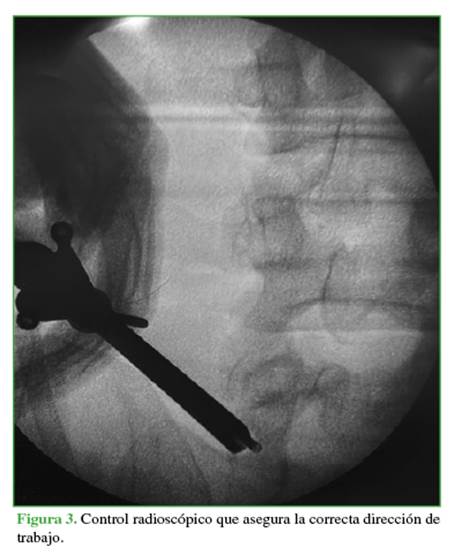

Hombre de 45 años de edad que concurre a la consulta por una radiculopatía de L5 izquierda, de siete meses de evolución (escala analógica visual 8/10). En el examen físico, la movilidad y la fuerza están conservadas y no hay déficit motor. En la resonancia magnética, se visualiza una hernia extraforaminal en el espacio L5-S1 del lado izquierdo (Figura 1). El paciente refiere haberse sometido a 20 sesiones de terapia física, dos bloqueos radiculares selectivos de L5-S1 y haber recibido tratamiento con pregabalina 75 mg por tres meses, con mejoría de los síntomas, pero de corta duración. Ante la falta de respuesta al tratamiento conservador, se le propone una discectomía endoscópica.